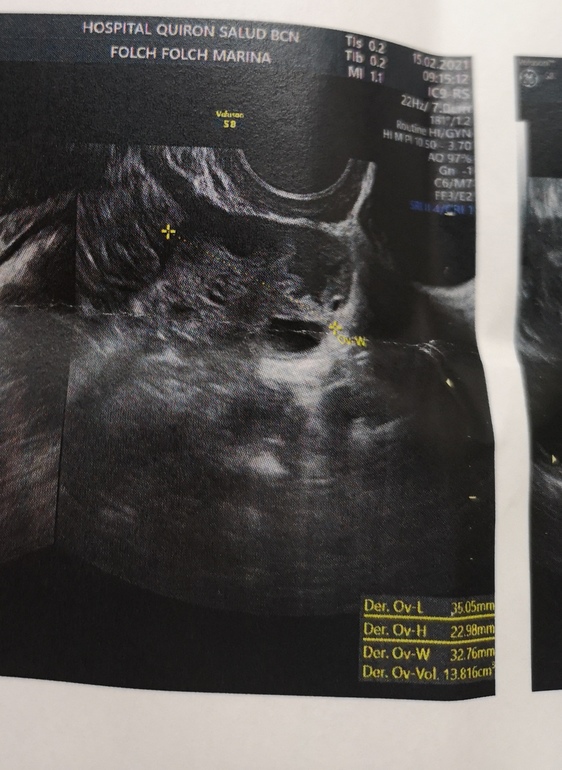

Девочки по узи О не было, так сказала врач. Но я думаю что все же была или в день узи или за день до узи. Скажите пожалуйста это может быть ЖТ? Или что это такое в виде кляксы? Это пя и он увеличен в объёме в два раза. Бт высокая, как во второй фазе.

По снимкам на жт не похоже, скорей всего овуляции не было. Я не врач, но за 2 года научилась определять, снимков дофига. У меня как раз проблема, овуляция происходит непонятно когда, хожу на узи по 3 раза в поисках жт и очень часто фолликул😢. Ваш фолликул лютеинизоровался, мне кажется.

А кляуса действительно похожа на жт, у меня ровные кружочки были на узи, а у вас прям как надо)

Не эксперт, но позволю предположить. Под "кляксой " ДФ, возможно он дорос и совулировал. Сама "клякса" это конечно не разрыв фолликула. Поэтому О сместилась, а что в УЗИ по поводу Фоликов написано?

По ущи написано что у меня 23 фоликула и все. Я не знаю где она их нашла в таком количестве. И объем пя увеличен в 2 раза, у меня такой объем бывает там где овуляция обычно. Сказала О не было и что эндометрий уже готовится к М, это было 8 дней назад. М не пришли и началась по бт и выделениями вторая фаза.

У меня в этом цикле так. По узи О нет, фолликул стал меньше. А по снимку я явно увидела ЖТ. Переделала узи, ЖТ было)